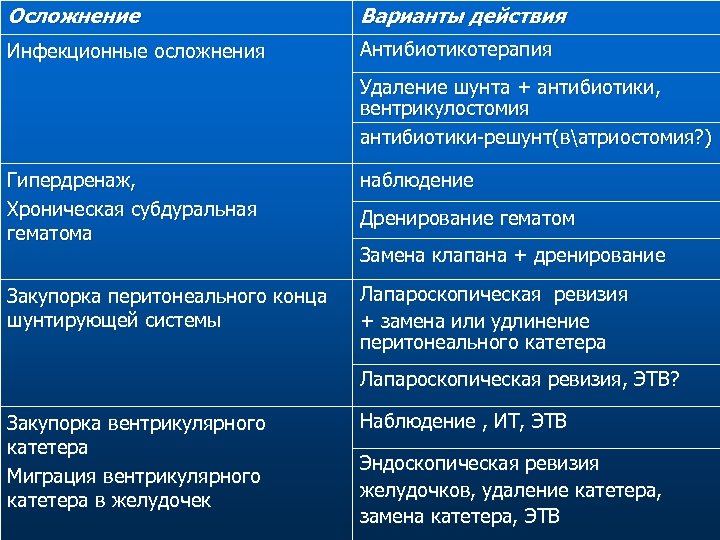

Осложнение Варианты действия Инфекционные осложнения Антибиотикотерапия Удаление шунта + антибиотики, вентрикулостомия антибиотики-решунт(ватриостомия? ) Гипердренаж, Хроническая субдуральная гематома наблюдение Закупорка перитонеального конца шунтирующей системы Лапароскопическая ревизия + замена или удлинение перитонеального катетера Дренирование гематом Замена клапана + дренирование Лапароскопическая ревизия, ЭТВ? Закупорка вентрикулярного катетера Миграция вентрикулярного катетера в желудочек Наблюдение , ИТ, ЭТВ Эндоскопическая ревизия желудочков, удаление катетера, замена катетера, ЭТВ